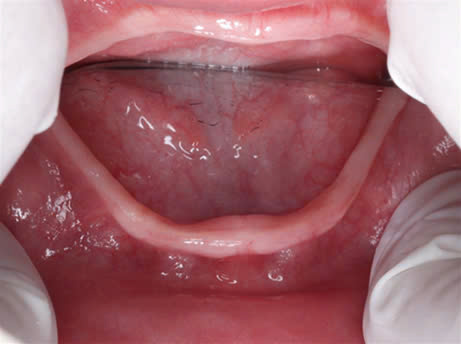

Hình 3: Ảnh chụp trong miệng

Tùy mức độ từ nhẹ đến nặng của bệnh mà có biểu hiện ở răng từ thiếu một vài răng đến thiếu nhiều răng đến không có răng.

Đối với điều trị răng cho các bé từ giai đoạn ban đầu hàm giả tháo lắp giúp phục hồi chức năng ăn nhai cũng như phát âm, giao tiếp cho trẻ 1 cách tốt nhất.

Làm hàm giả tháo lắp cho trẻ.

Nhờ hàm giả mới này, khuôn mặt của trẻ thay đổi về ăn nhai cũng như mặt thẫm mỹ.